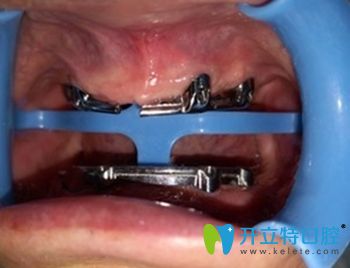

(老爸在鼎植口腔做種植牙的手術(shù)圖)   ↓

慈溪鼎植口腔種植牙術(shù)中照

做手術(shù)的是陳炳霖院長(zhǎng),還有一位謝醫(yī)生,聽說也是個(gè)醫(yī)學(xué)碩士。畢竟這么貴,要做一定得做好,醫(yī)生肯定是個(gè)關(guān)鍵。手術(shù)過程我們沒有在旁邊,這張圖片還是從門診電腦上拍的,這個(gè)工具好像叫導(dǎo)板還是啥名字。